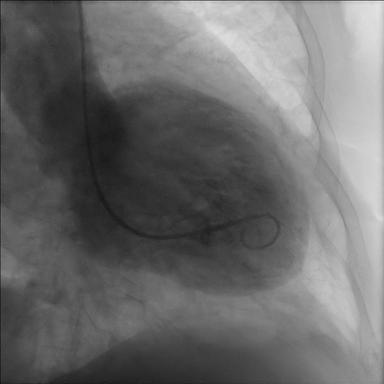

Þegar komið var að Esjurótum varð verkurinn sterkur og hún kastaði upp, en ákvað að reyna að hvíla sig í bílnum. Verkurinn gekk á endanum eitthvað tilbaka og upp Esjuna fór hún. Það var ekki fyrr en nokkrum dögum seinna að hún ákvað að fara á heilsugæslu til að láta skoða sig þar og var send áfram á bráðamóttöku. Þaðan fór hún svo í hjartaþræðingu, með sömu einkenni og koma fram við hjartaáfall en niðurstaðan var sú að vegna uppsafnaðs álags og streitu hafði myndast ástand sem kallað er harmslegill (Takotsubo / broken heart syndrome) og er heilkenni sem myndast við mikla streitu, áföll eða sorg, ástand sem konum er hættara við en körlum.

Harmslegill heitir á frummálinu Takotsubo sem er heiti á krabbagildru sem sjá má hér til hliðar við röntgenmyndirnar. Heitið helgast af löguninni sem er sú sama og téðrar gildru

Harmslegill eða Takotsubo er tímabundin afturkræf truflun á samdrætti hjartans sem lýsir sér þannig að hjartað líkist blöðru. Heilkenninu var fyrst lýst árið 1990 í Japan hjá 64 ára gamalli konu sem fékk brjóstverk og var hjartalínuritið með breytingum sem líktust bráðri kransæðastíflu.

Kransæðarnar voru hinsvegar eðlilegar en vinstri slegill dróst óeðlilega saman og gekk samdráttarskerðingin tilbaka á tveimur vikum. Heilkennið var nefnt Takotsubo eftir japanskri kolkrabbagildru því lögun hjartans líktist gildrunni þegar það sló í þessu ástandi. Heilkennið hefur verið kallað ýmsum nöfnum á ensku m.a. broken heart syndrome, stress cardiomyopathy og apical ballooning syndrome en á íslensku hefur það verið nefnt harmslegill.